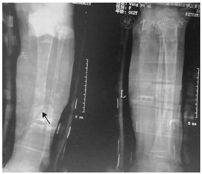

女性,年龄为19个月,因"左腿胫骨骨折1 d"于2013-10-04入青岛市城阳古镇正骨医院治疗。病史采集:患儿12个月时因摔倒发生右腿胫骨骨裂,15个月时因滑倒发生右尺骨骨折。家族史:患儿母亲为篮巩膜,2~3岁时因摔倒发生上臂骨折,8~9岁时因跳绳发生足踝骨折,20岁时因摔倒致右手鹰嘴骨折;父亲正常;外曾祖母、外祖母、2位姨外祖母及其中1位姨外祖母之子均为篮巩膜,除该子外,其余4人均有骨折病史。全家族无听力异常及皮肤改变,牙龄发育正常。入院查体:体质量为9.2 kg,身高为76 cm,四肢短,智力发育正常,额骨宽且向前突出,枕骨向后突出,前囟已闭,头围为45 cm,头部左右径为15 cm,前后径为13 cm,双眼巩膜呈淡蓝色,听力正常,心、肺、腹查体(一),肌力、肌张力正常。辅助检查:X射线摄片结果提示为左腿胫骨斜型骨折(图1)。ALP为181 U/L(正常值为<500 U/L),血Ca2+及P3-均在正常值范围内,甲状旁腺激素、生长激素水平均正常。入院诊断:左腿胫骨骨折。入院后给予患儿手法复位后石膏外固定治疗,治疗7 d后病情稳定出院,出院后2周复查X射线摄片结果示骨折处对位良好,出院后4个月骨折完全恢复。为进一步明确诊断,患儿到青岛市市立医院门诊就诊,经采集病史并根据患儿及其家族特殊病史高度怀疑患儿为成骨不全症(osteogenesis imperfecta,OI)。